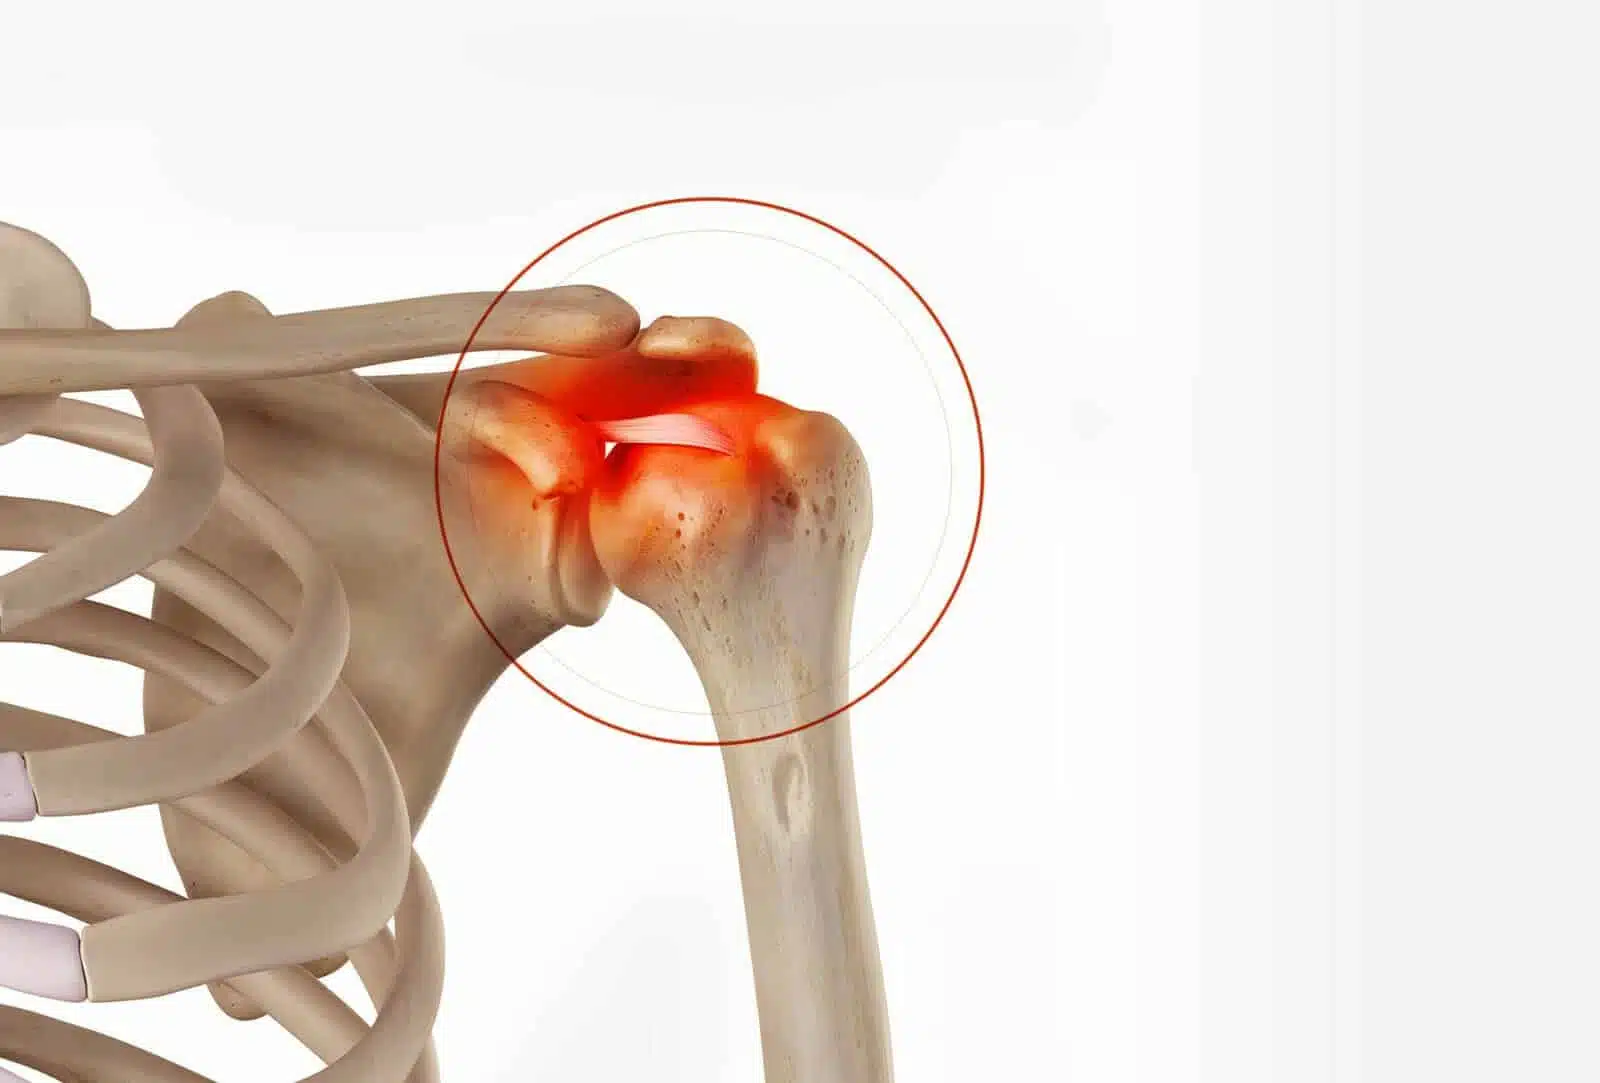

A trauma to the shoulder can cause the rupture of these ligaments, so they no longer hold the acromioclavicular joint together. Gravity pulls the shoulder and the scapula downwards and the muscles pull the collarbone upwards (figure 2 and photo 1). We thus talk of acromioclavicular luxation that can result in fatigability, pain and a visible deformation.

An acromioclavicular luxation does not resolve itself spontaneously, and in the absence of a surgical procedure the collarbone remains ascended. Furthermore, the ligaments do not heal in an effective position and so the collarbone is not held in place.

This high position of the collarbone, apart from the aesthetic inconvenience, can cause permanent discomfort and fatigability when carrying out daily activities or sports.